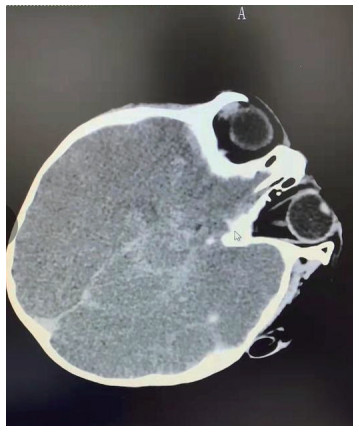

| 图 2 2月22日颅脑MRI |

图 1为颅内弥漫脑实质肿胀,脑沟脑回显示不清,脑室受压,部分脑沟内可见高密度影,右侧小脑幕密度增高。中线结构居中。副鼻窦内见软组织密度影。图 2为大脑皮层、小脑及脑干形态肿胀,呈稍长T2信号影,有类似束带征。图 3为后颅窝去骨辨减压+小脑部分切除术后复查: 脑疝征象明显好转。